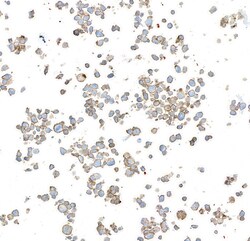

A700-063-T ICC

Full details

Method:

Other validation